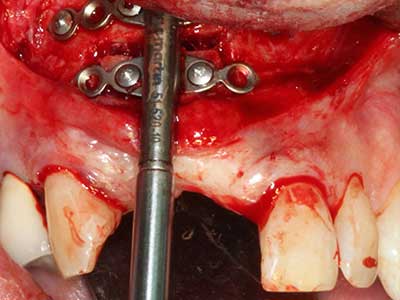

Sollen chirurgische Eingriffe mit unmittelbarer Knochenbeziehung an empfindlichen Strukturen wie Blutgefäßen oder Nerven erfolgen, so bergen rotierende Instrumente ein erhebliches Potential an iatrogener Schädigung. Gerade bei Nervdarstellungen nach iatrogener Schädigung, oder aber im Zuge einer Nervlateralisation für resektive und rekonstruktive Eingriffe oder Implantatinsertionen können piezoelektronische Geräte hilfreich sein Knochendeckel zu präparieren und nervnahe Hartgewebsanteile zu entfernen (Abb. 17-20). Ein leichter Kontakt des Nervstrangs zur Piezospitze bleibt dabei in der Regel folgenlos – allerdings kann eine unvorsichtige Vorgehensweise mit sägeartigen Bewegungen bzw. Ansätzen bei noch vorhandener knöcherner Unterlage durchaus temporäre oder aber auch permanente Nervschädigungen verursachen. Das Risiko einer solchen Schädigung wird jedoch als wesentliche geringer eingeschätzt als unter Anwendung von Säge- oder Fräsinstrumenten (Pereira, Gealh et al. 2014).

Abb. 18: Präparation eines Kortikalis-Deckels mit der Piezo-Knochensäge (Piezomed, W&H).

Abb. 19: Operationssitus nach Neurolyse und Osteomentfernung.

Abb. 20: Der entnommene Knochendeckel wird readaptiert und durch eine Osteosyntheseschraube (KLS Martin, Tuttlingen) fixiert.